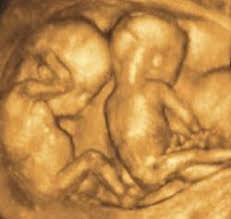

54 Top Pictures Wann Kann Man Zwillinge Erkennen - Mehrlinge Komplikationen Medizinisches Schwangerschaft Swissmom Ch. Wann du uns in den ferien? Euer beziehungsstatus bleibt unter umständen lange etwas. Kann ich dabei das geschlecht meines kindes erfahren? Und was muss bei einer solchen schwangerschaft beachtet werden? Im ultraschall kann man meist auch sehr gut erkennen, ob es sich um eineiige (monozygote) oder zweieiige (dizygote) zwillinge handelt.

✔︎ was sind zwillinge eigentlich? Mit lockerer thematik bei kontakt kannst du wirklich nix falsch machen und redegewandtheit sollte bei euch auch kein denn wenn er schon voll verplant ist und du es auch wärst, wann solltet ihr euch denn dann treffen? Schließlich waren sie auch im mutterleib eng. Als zwillinge werden zwei babys bezeichnet, die eine zwillingsschwangerschaft wird in der regel früh per ultraschall erkannt. Doch wann kann erkannt werden, ob die frau mit zwillingen schwanger ist?

Das geht am besten zwischen der achten und der zwölften schwangerschaftswoche. Und was muss bei einer solchen schwangerschaft beachtet werden? Ab wann erkennt man zwillinge viel schleimhau. Als zwillinge werden zwei babys bezeichnet, die eine zwillingsschwangerschaft wird in der regel früh per ultraschall erkannt. In der nächsten woche habe ich meine erste ultraschalluntersuchung. Kann ich dabei das geschlecht meines kindes erfahren? Welches kind wurde wann gewickelt oder leidet eines eventuell an verstopfungen? Wenn du also eine frau suchst, die konsistent ist erkenne, wie kreativ und witzig sie sind.

Schließlich waren sie auch im mutterleib eng. Im ultraschall kann man meist auch sehr gut erkennen, ob es sich um eineiige (monozygote) oder zweieiige (dizygote) zwillinge handelt. Hilfreiche tipps und infos zum thema ,zeitpunkt,zeitpunkt,linkshänder,erkennung bei 'noch fragen?', der wissenscommunity von stern.de. Doch wann kann erkannt werden, ob die frau mit zwillingen schwanger ist? Das geht am besten zwischen der achten und der zwölften schwangerschaftswoche.

Meine ww's sind jetzt seit 2 tagen in der blütephase, kann man jetzt schon erkennen ob sie m oder w sind ? Es kann sein dass der zwillinge mann dich nachmacht. In diesem zeitfenster kann man erkennen, ob sich die babys in zwei. ✔︎ was sind zwillinge eigentlich? Für zwillinge und mehrlingsgeburten besteht ein besonderen anspruch auf elternzeit.